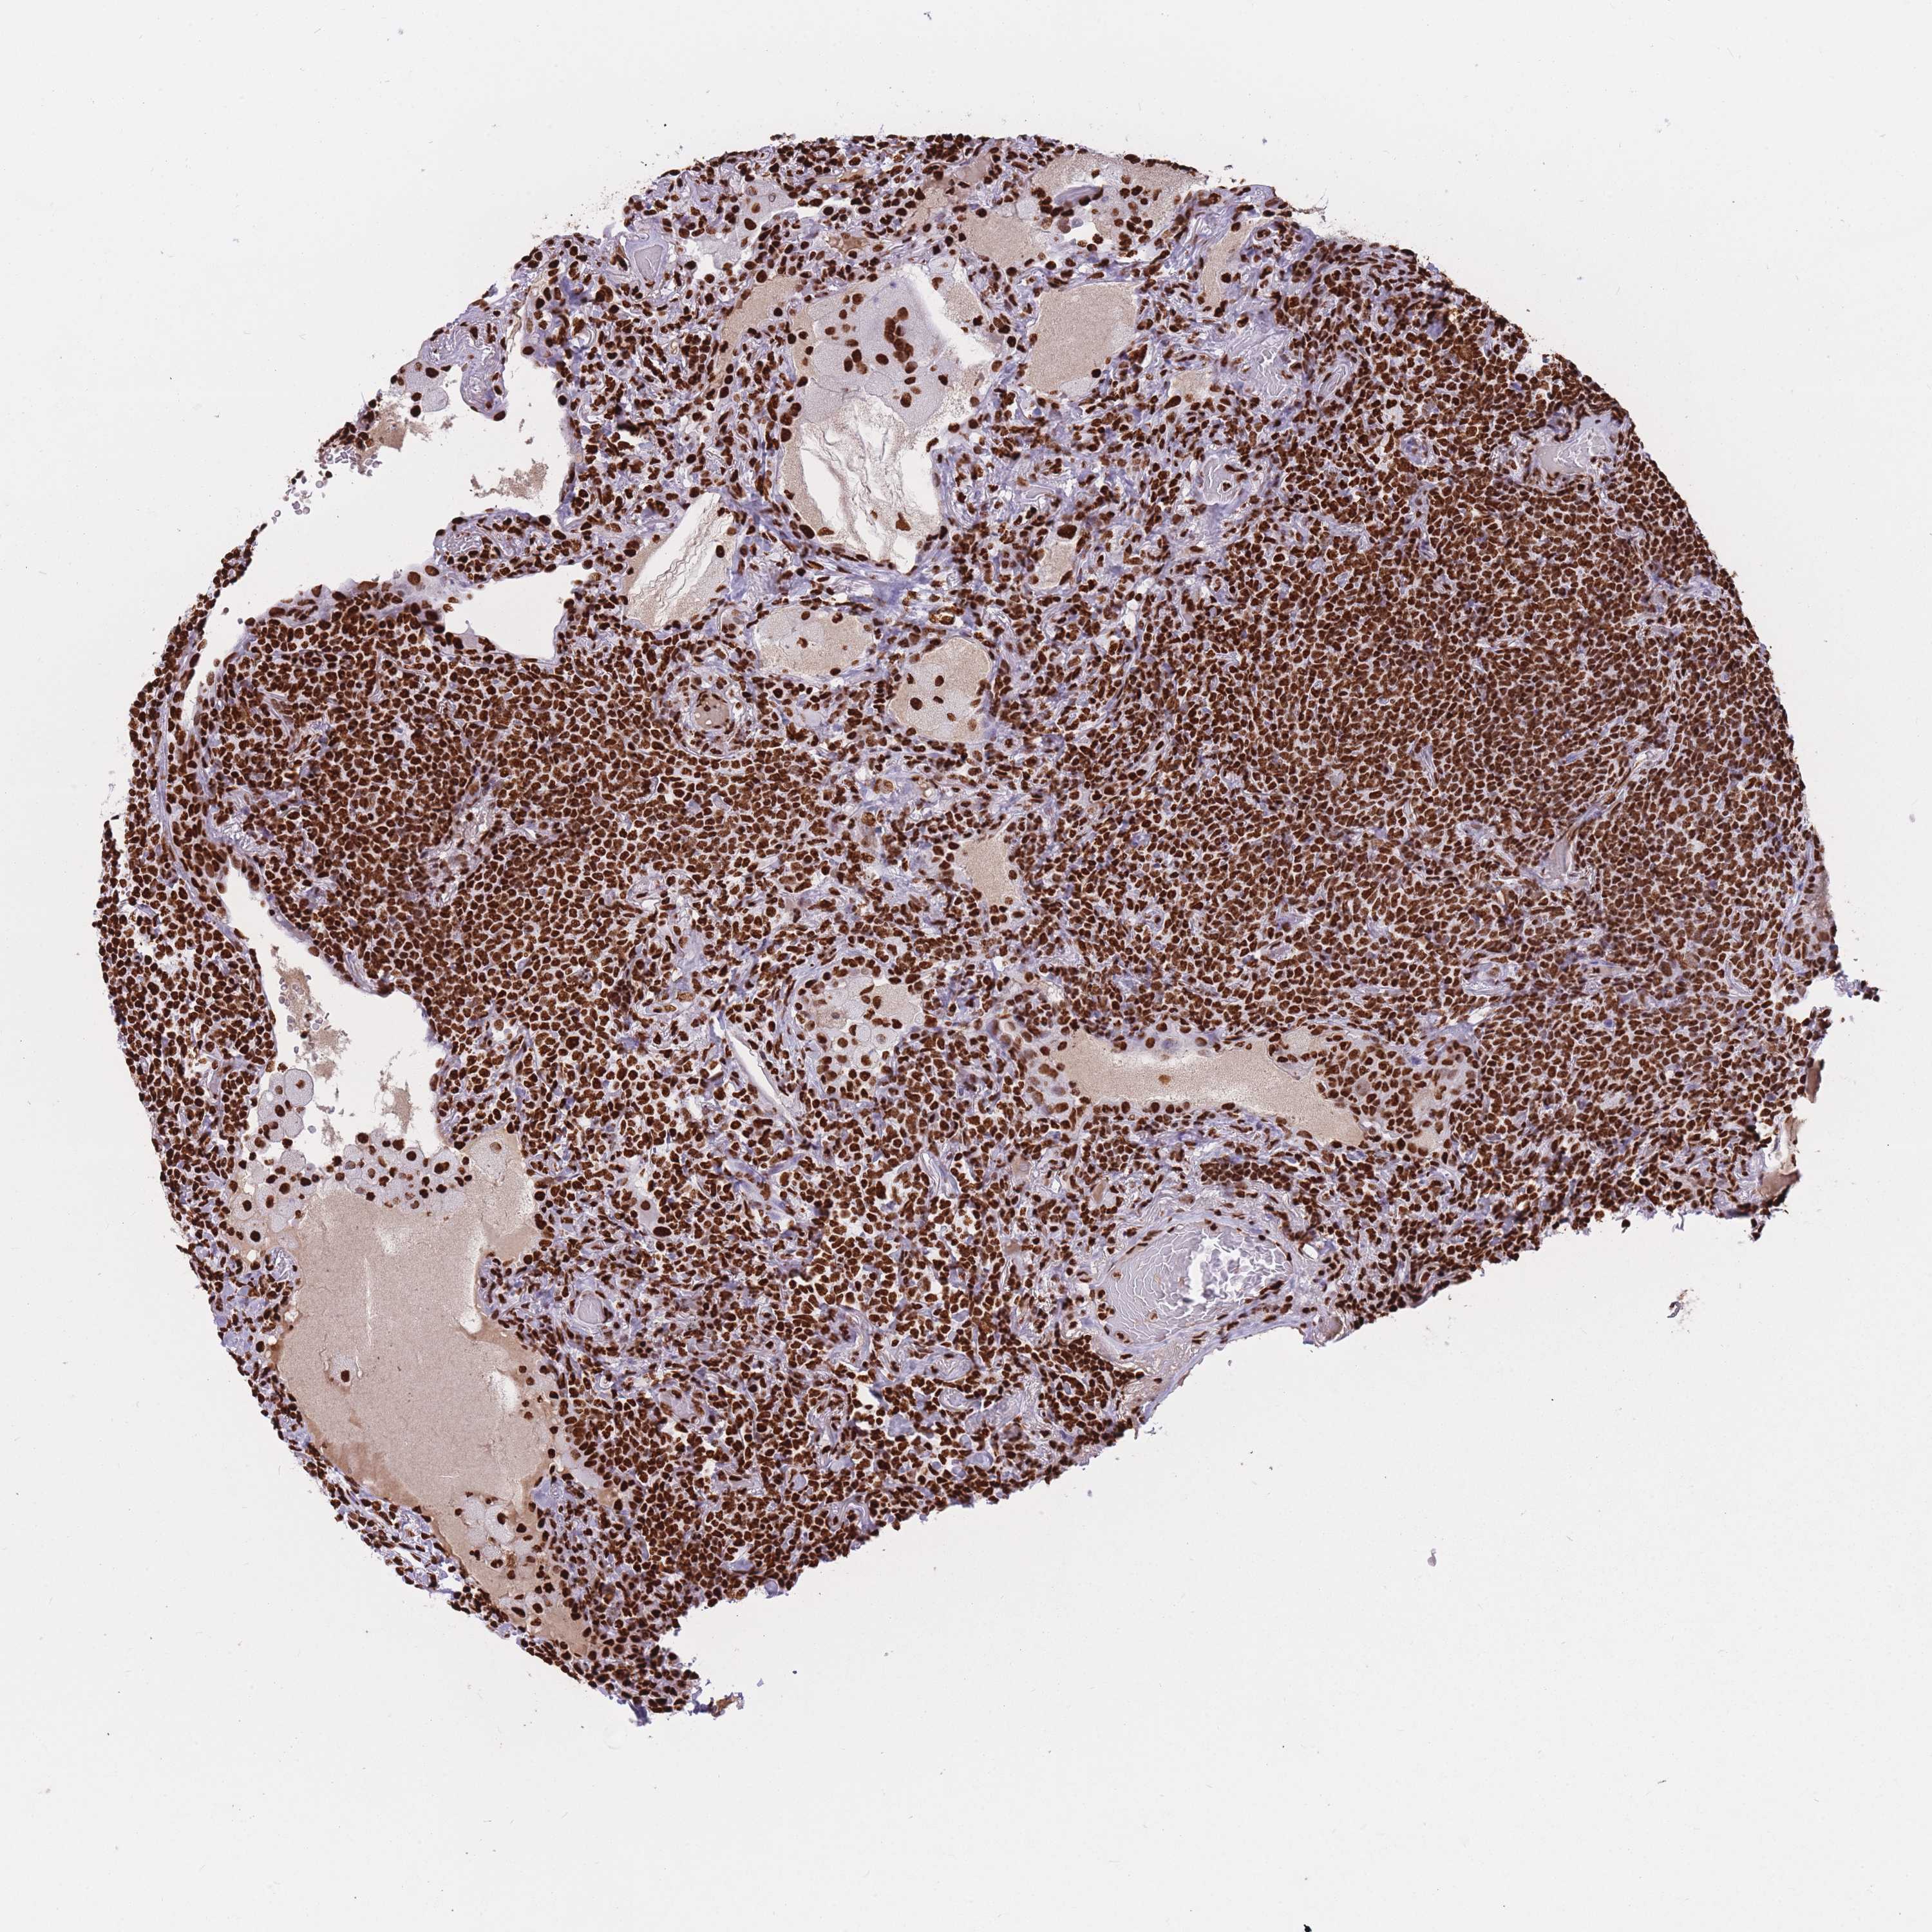

LYMPHOMA - Protein expressioni

A mouse-over function shows sample information and annotation data. Click on an image to view it in a full screen mode. Samples can be filtered based on level of antibody staining by selecting one or several of the following categories: high, medium, low and not detected. The assay and annotation is described here.

Antibody staining in the annotated cell types in the current human tissue is reported as not detected, low, medium, or high, based on conventional immunohistochemistry profiling in selected tissues. This score is based on the combination of the staining intensity and fraction of stained cells.

Each image is clickable and will lead to virtual microscopy that enables deeper exploration of all samples and also displays staining intensity scores, fraction scores and subcellular localization as well as patient and tissue information for each sample.

Antibody HPA049475

Staining

High

Strong

>75%

Nuclear